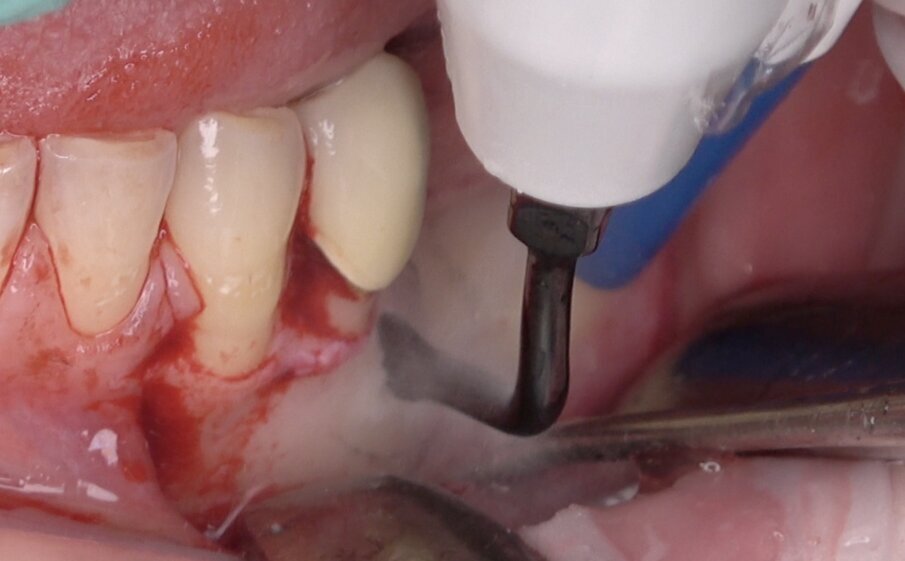

Fig. 5 - Utilizzo del terminale piezoelettrico (Esacrom) per creare il box osseo che permettere di accedere al dente incluso.

Possiamo dunque concludere che il piezo è uno strumento che permette di svolgere in sicurezza atti chirurgici molto delicati, grazie alla precisione di taglio e all’inefficacia sui tessuti molli. Molti vantaggi sono offerti anche dalla capacità di mantenere un campo operatorio con il controllo dell’emostasi, aspetto clinico di notevole importanza soprattutto quando ci si trova a operare in porzioni ossee profonde con residui radicolari di dimensioni ridotte. Il problema in passato però è sempre stato relativo alla lentezza di taglio ma attualmente i nuovi inserti risultano essere sempre più efficienti su diversi tipi di tessuto. Infatti Grazie al nuovo “device” della ditta italiana ESACROM è possibile raggiungere una potenza massima di 70 Watt permettendo di tagliare anche il dente agevolmente consentendo quindi di eseguire un approccio totalmente piezoelettrico.